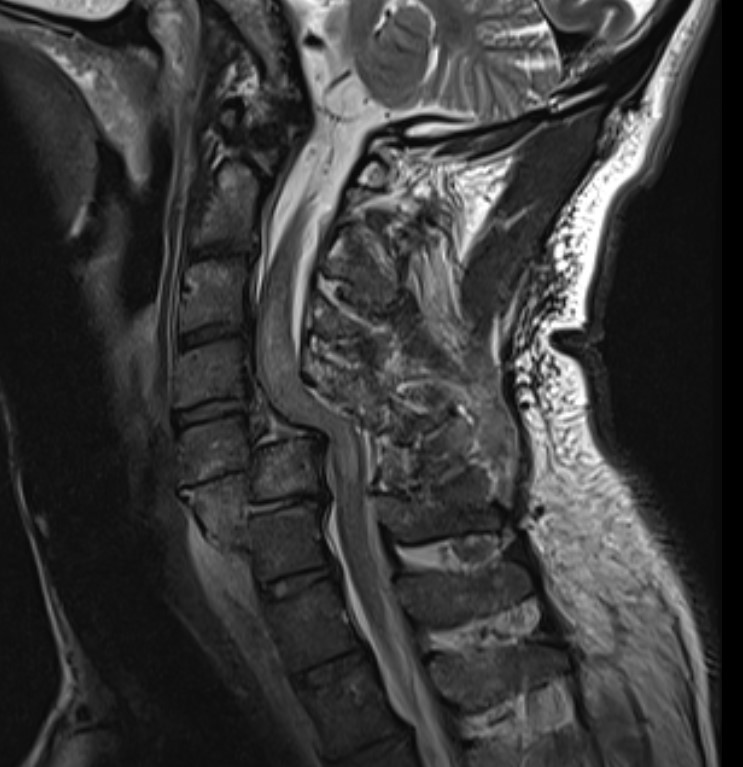

MRI

Look for herniated disc

- ? large disc could worsen neurology with skull traction / closed reduction

- ? indication for anterior approach / discetomy / fusion

Herniated disc on MRI seen after facet joint dislocation